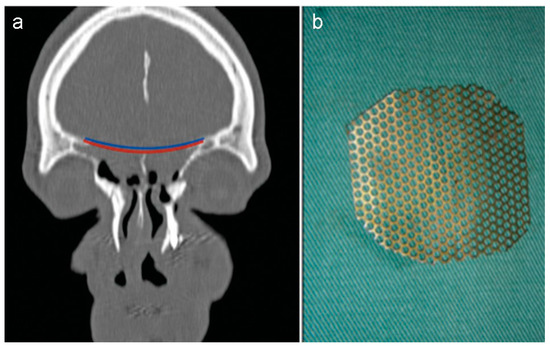

Figure 6. (a) The planning of the reconstruction included the placement of a pericranial flap (red layer) on the defect, the titanium mesh (blue layer). (b) The titanium mesh was contoured previously for a more accurate implant.

Faced with this diagnosis and due to a large bilateral bone defect, another surgery was proposed to reconstruct the bone defect and reduce the protrusion of the brain using “sandwich” technique (Figure 6a). This technique aims to cover the defect and reinforce the anterior cranial base using local or free flaps with a tailored piece of titanium mesh, respectively.

Before the second procedure, the dimensions of bone defect were measured using 3D computer software and the titanium mesh contoured for a more accurate implant (Figure 6b). Thus, the operation was planned as shown in Figure 7. The planned reconstruction started with the same steps of the first procedure. Then, the contoured mesh was placed over the anterior skull base defect with the help of 4-mm screws (Figure 8a,b).